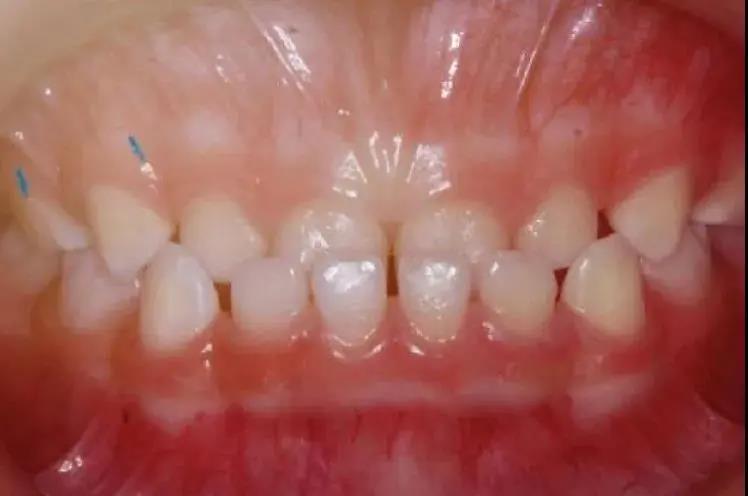

例如孩子在咀嚼的時候

上門牙咬在下門牙的后方

(俗稱“地包天”)